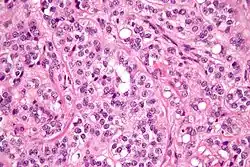

Micrograph of a Sertoli–Leydig cell tumour. The Leydig cells have abundant eosinophilic or light pink cytoplasm. The Sertoli cells have a pale/clear cytoplasm. H&E stain.

The tumour is subdivided into many different subtypes. The most typical is composed of tubules lined by Sertoli cells and interstitial clusters of Leydig cells.